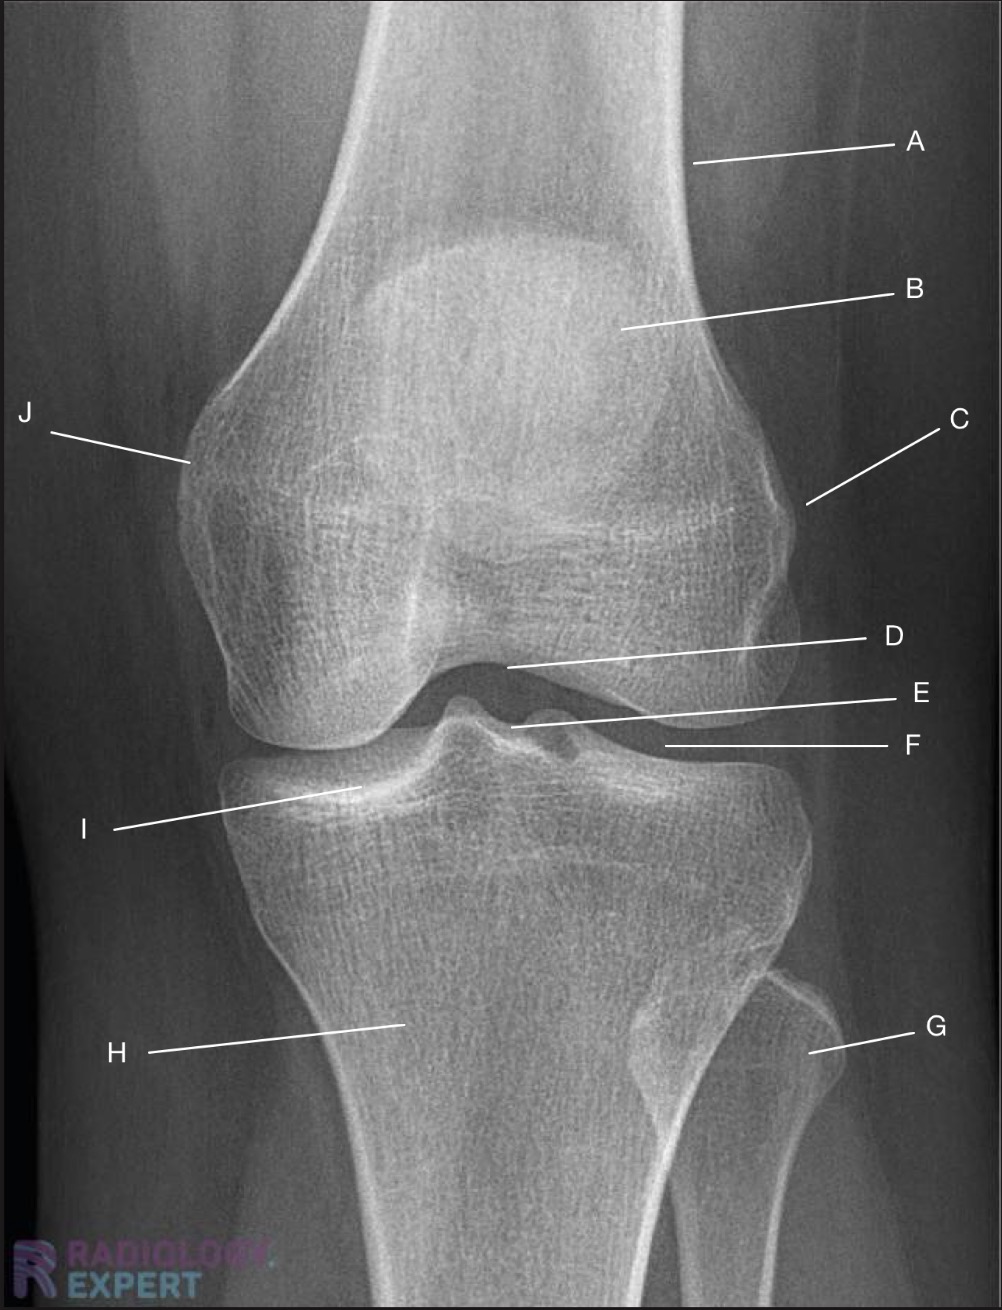

Name the projection.

Should it be repeated, if so why?

Lateral Knee

Yes. Patient is not in true lateral.

Fibular head and tibia are not superimposed.

Femoral condyles not superimposed

Label the image

A) Femur

B) Patella

C) Intercondylar eminence

D) Tibia

E) Fibular shaft

F) Fibular neck

G) Fibular head

H) Femorotibial joint

I) Femoral condyles